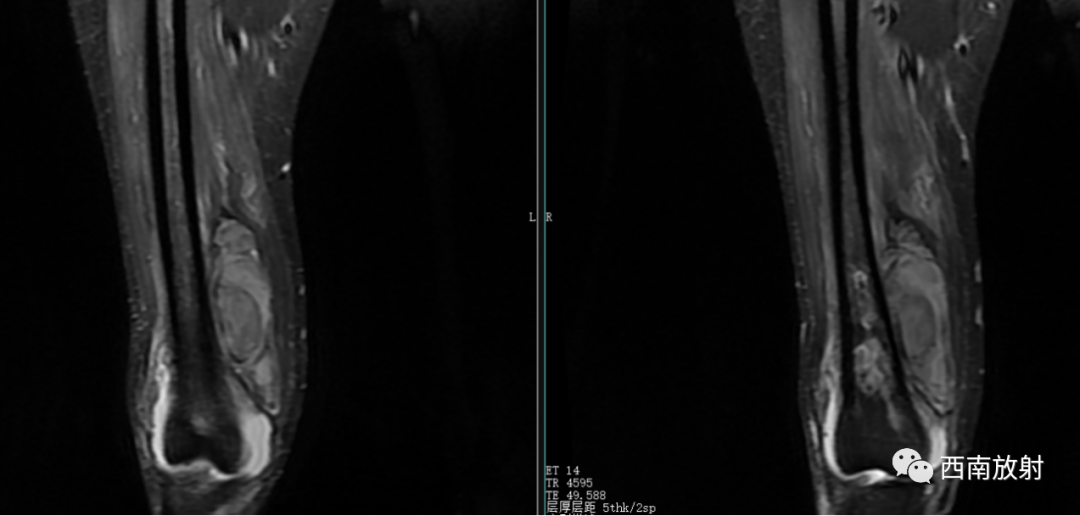

现病史:患者于2021年8月17日开始出现右膝关节疼痛,无畏寒发热、恶心呕吐、咳嗽咳痰,无破溃、流脓,于8月20日在我院急诊科就诊,考虑关节炎,予口服双氯芬酸钠缓释片及泼尼松等药物治疗,无好转,随后转到天等县中医院就诊,予行右膝关节抽液及外敷中成药治疗(具体不详),4天前开始出现解黑便,每日1次,每次量约200g,伴有头晕、乏力,无腹痛、呕血、昏迷及呼吸困难等。今来院就诊,在门诊发现血压偏低,85/56mmHg,右膝关节抽出45ml的红色积液,右膝关节MRI示有骨髓炎,生命征不稳定,有转入我科指征,我科会诊后转入治疗。患者病后精神、睡眠差,未进食,大便如上述,小便色黄,量尚可,体重无明显变化。

大体病理:右大腿中下段内侧骨膜外见一腔隙,约3X3X4cm,内有较多血凝块,有少许脓液,股骨下段周围有少许脓液,少量疤痕形成,右膝关节内有少许脓液,见有少许脓苔,右骨髓腔未见破坏,骨髓腔内有少许脓液,已被疤痕织包裹。

诊断:慢性骨髓炎,周围软组织脓肿。

CT显示骨破坏、脓肿、死骨及骨膜增生、骨质增生硬化,呈骨小梁密度增高、模糊,髓腔密度增大、狭窄,皮质增厚。MRI显示早期骨髓内广泛分布的斑片异常信号,与邻近正常骨髓信号相比较,T1WI信号减低,T2WI信号增高,脂肪抑制T2WI 或STIR 等序列上病变显示更清楚,骨皮质周围软组织内呈弥漫分布的T1WI低信号及T2WI高信号影,边界模糊。出现骨膜反应,骨皮质不规则破坏,脓肿及死骨形成。